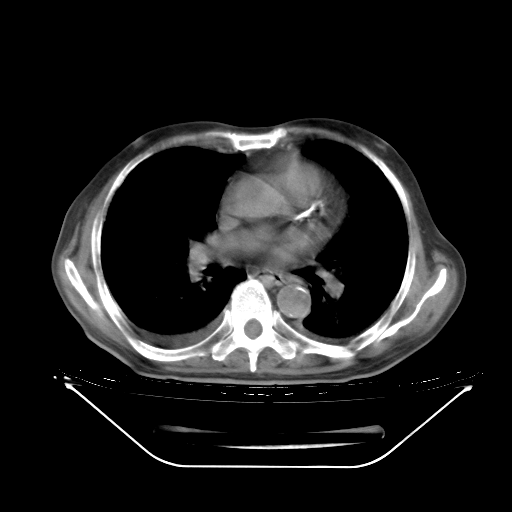

胸腹部CT,诊断意见:左上肺叶钙化灶、左侧胸膜局限性增厚并钙化、胆囊炎。描述部分肺组织呈磨玻璃样改变。